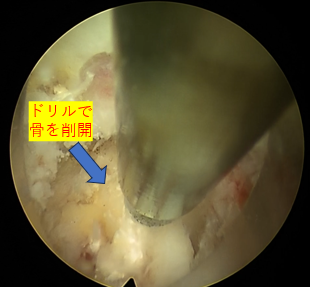

| 治療内容と方針 | 右下肢内側の痛み、しびれは後方固定除圧後の合併症である隣接椎間障害によるもので、右L4/5椎間孔の狭窄症が原因だったので「PEL(脊柱管狭窄症内視鏡下術)」を実施。神経を圧迫している骨をドリルで削開しました。削開後は、椎間孔狭窄の圧迫が取れて右L4神経根が確認できました。 それと同時に、神経修復作用の効果を期待できる血小板由来の成長因子を注入する「PRP療法」を行いました。 なお、他院で手術したL5/Sの部位は再発がないので、そこの部位の治療は行っていません。 |